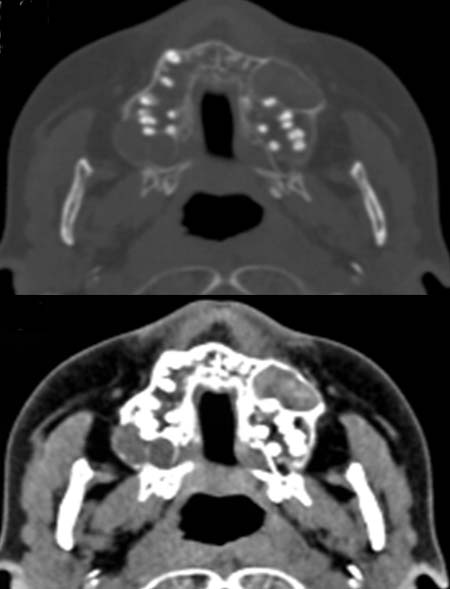

Patient, 56 Jahre alt, mit tastbarer Raumforderung im Bereich des Oberkiefers.

Basalzellnaevus mit auffälligen Hautveränderungen.

Im

Knochenfenster des CT (oberes Bild) kommen im Oberkiefer beidseits zystische

Raumforderungen zur Darstellung.

Im Weichteilfenster (unteres Bild) kommen diese Raumforderungen zum

Teil hyperdens, zum Teil hypodens zur Darstellung.

Gorlin-Goltz-Syndrom